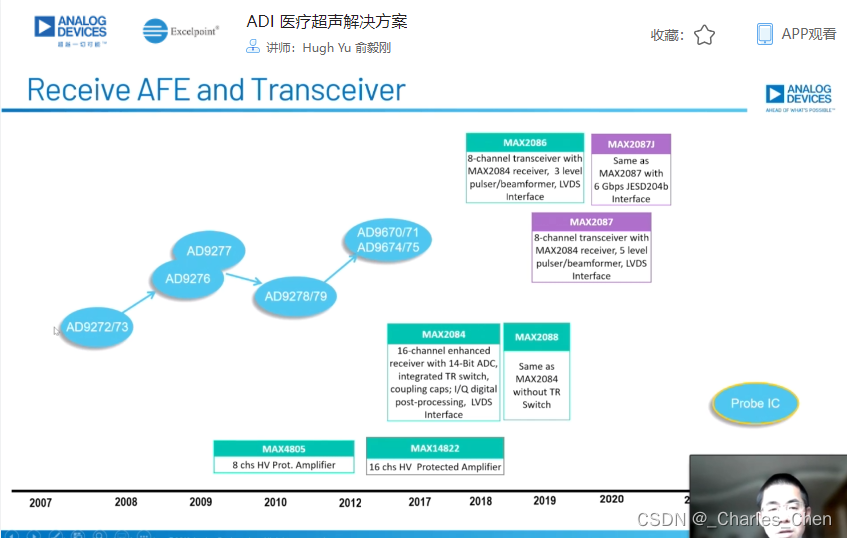

成像通道接收机

超声成像通道的接收机用于检测二维(2D)信号以及彩超流体成像所需的脉冲多普勒(PWD)信号和频谱PWD。接收机包括Tx/Rx开关、低噪声放大器(LNA)、可变增益放大器(VGA)、抗混叠滤波器(AAF)和模/数转换器(ADC)。